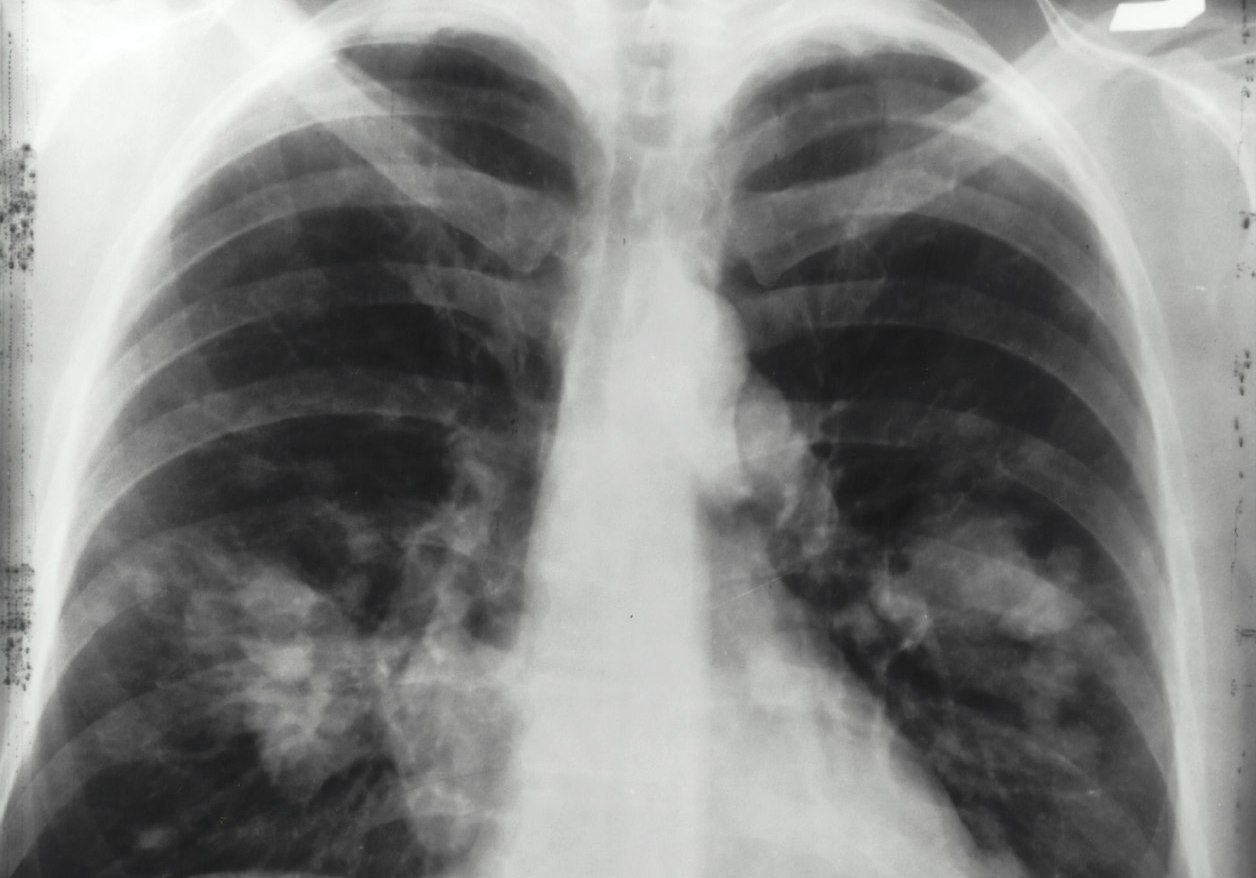

Болезнь вейперов добралась до Алтайского края

Заболевание все чаще стало поражать любителей вейпов и электронных сигарет.

Эксперты объясняют, что оно похоже на пневмонию, только среди специфических симптомов - дыхательная недостаточность.

Важно обратить внимание на следующие признаки: боль в груди, кашель, в том числе с мокротой, одышка, тахикардия, кровохаркание, проблемы с ЖКТ.

Говоря о дыхательной недостаточности, стоит отметить, что ее сложно лечить. Под угрозой поражения любой, курящий более двух месяцев. Особенно это касается подростков.